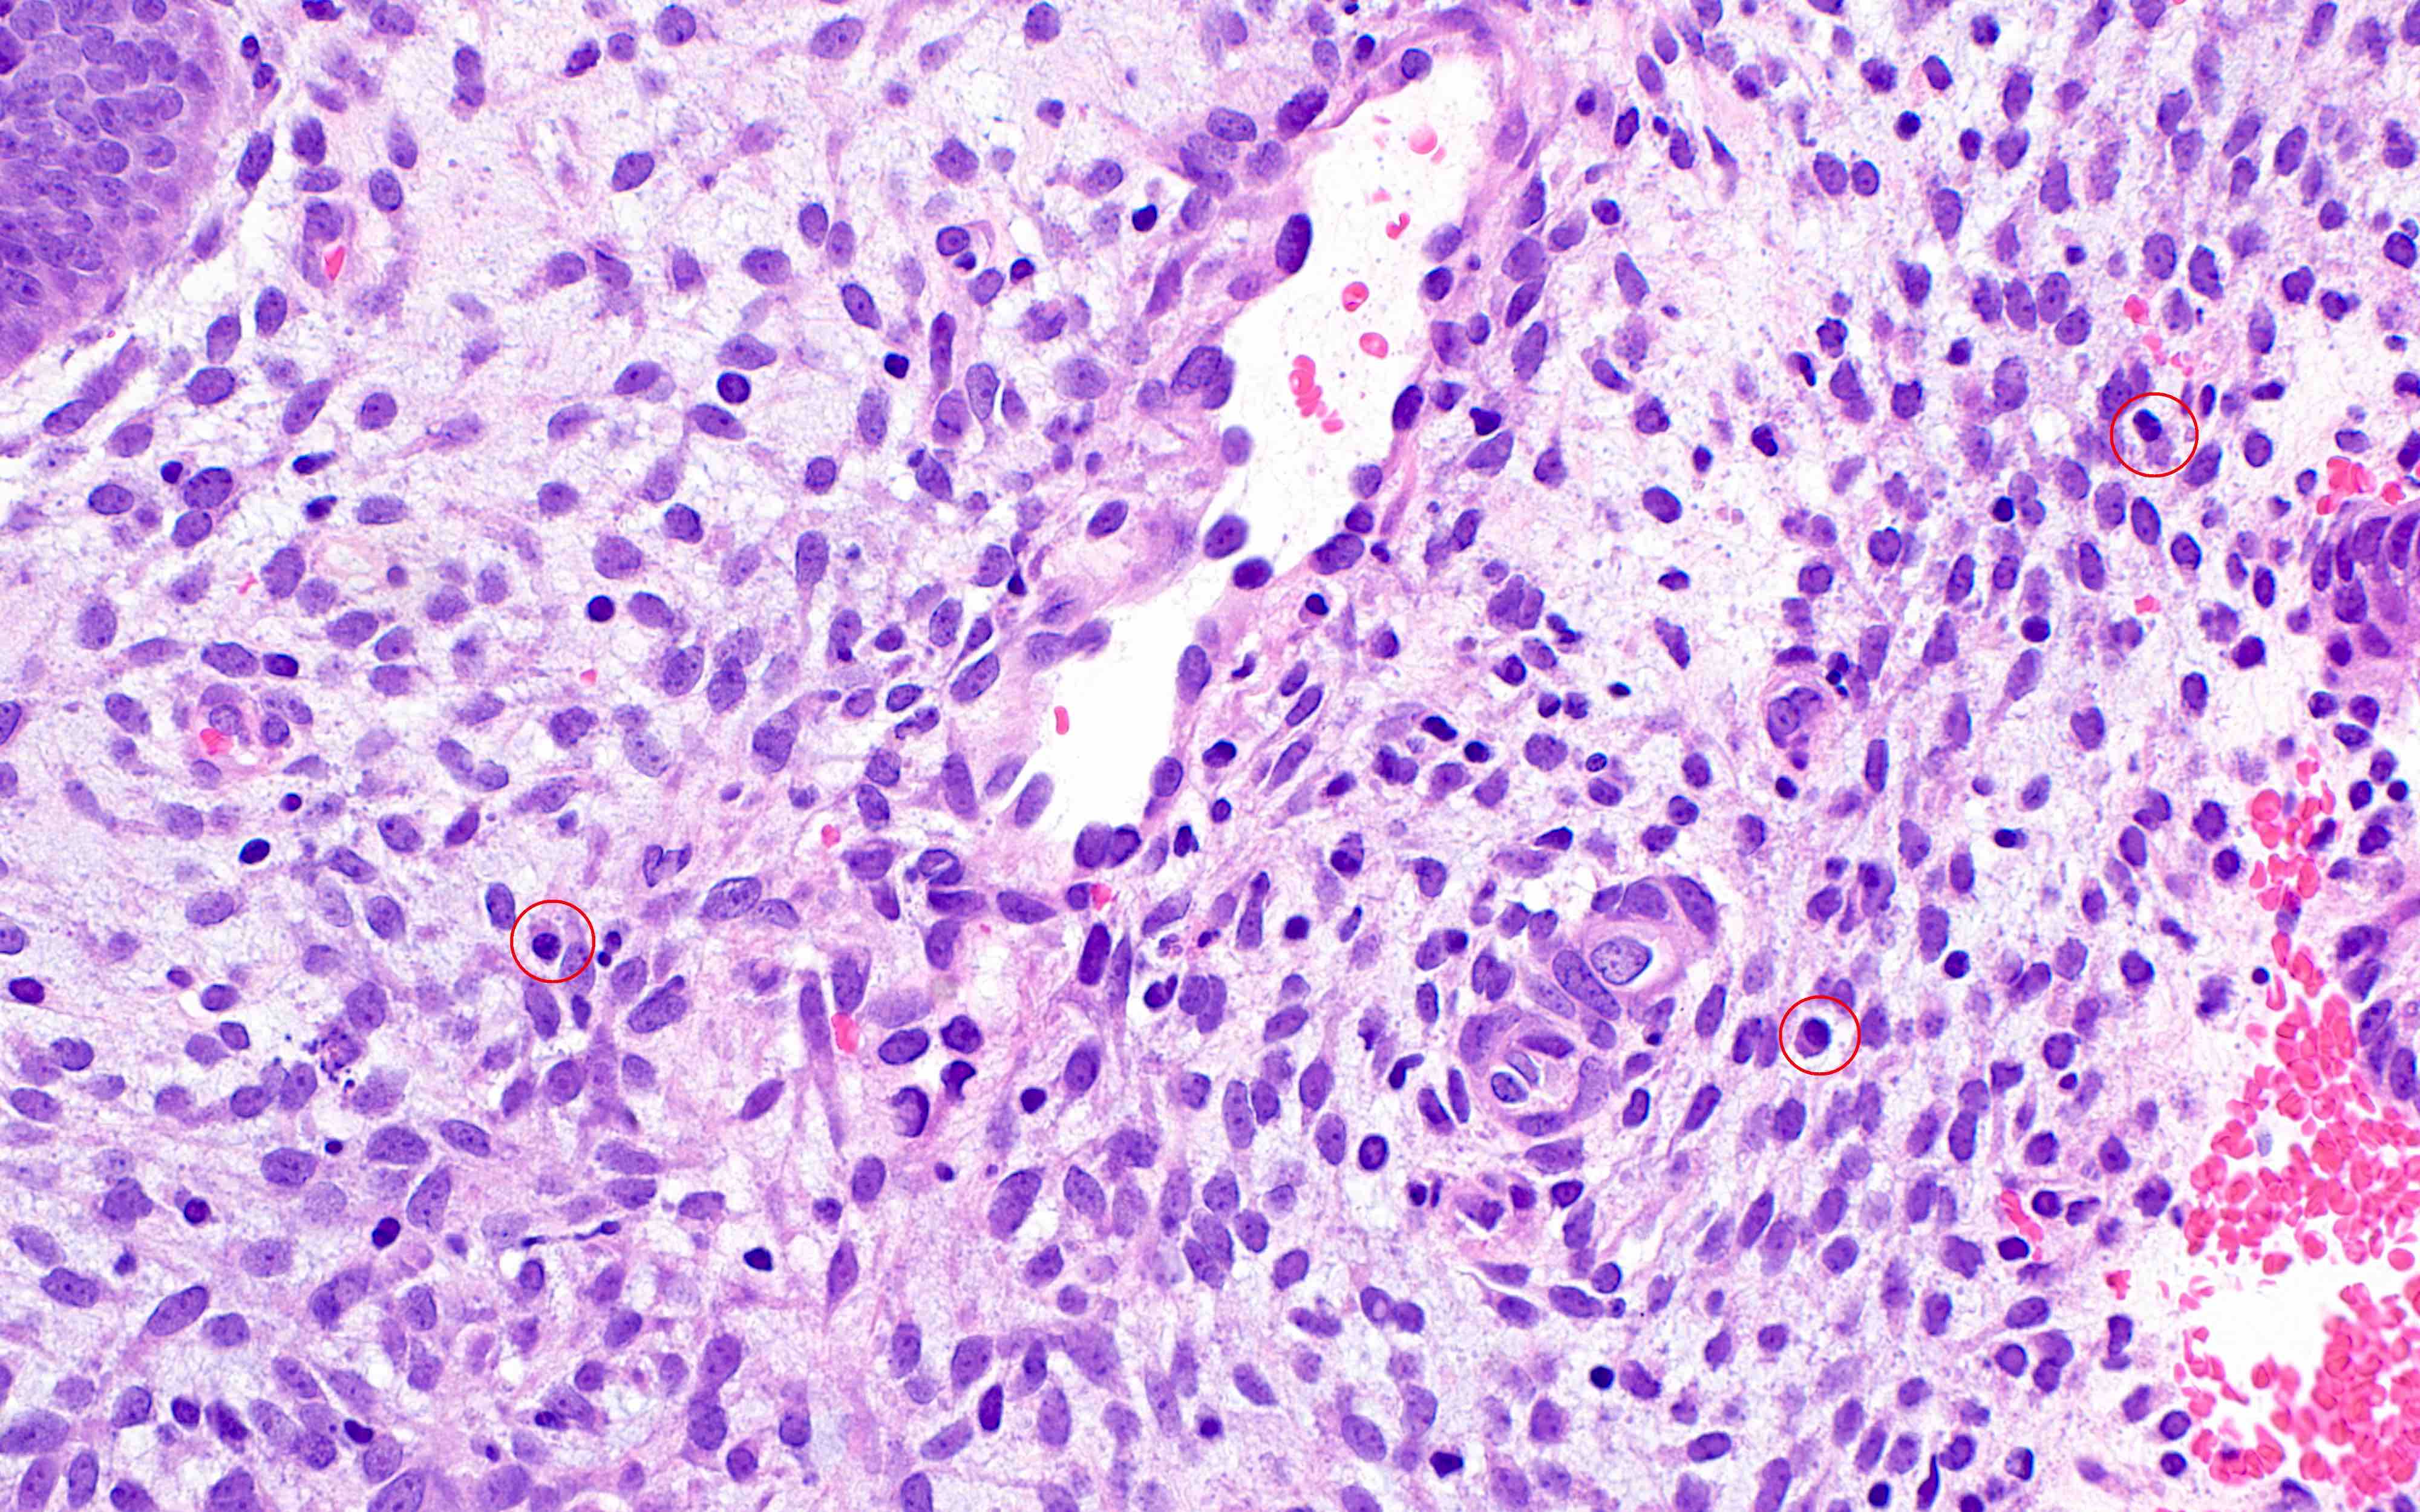

- Chronic endometritis

- Plasma cells (required) with or without lymphoid follicles

- Presence of eosinophils associated with plasma cells (Hum Pathol 2010;41:33)

- Spindled stromal cells

- Plasma cells (required) with or without lymphoid follicles

Microscopic (histologic) images

Contributed by Stephanie L. Skala, M.D. and Yuri Tachibana, M.D.

Chronic endometritis